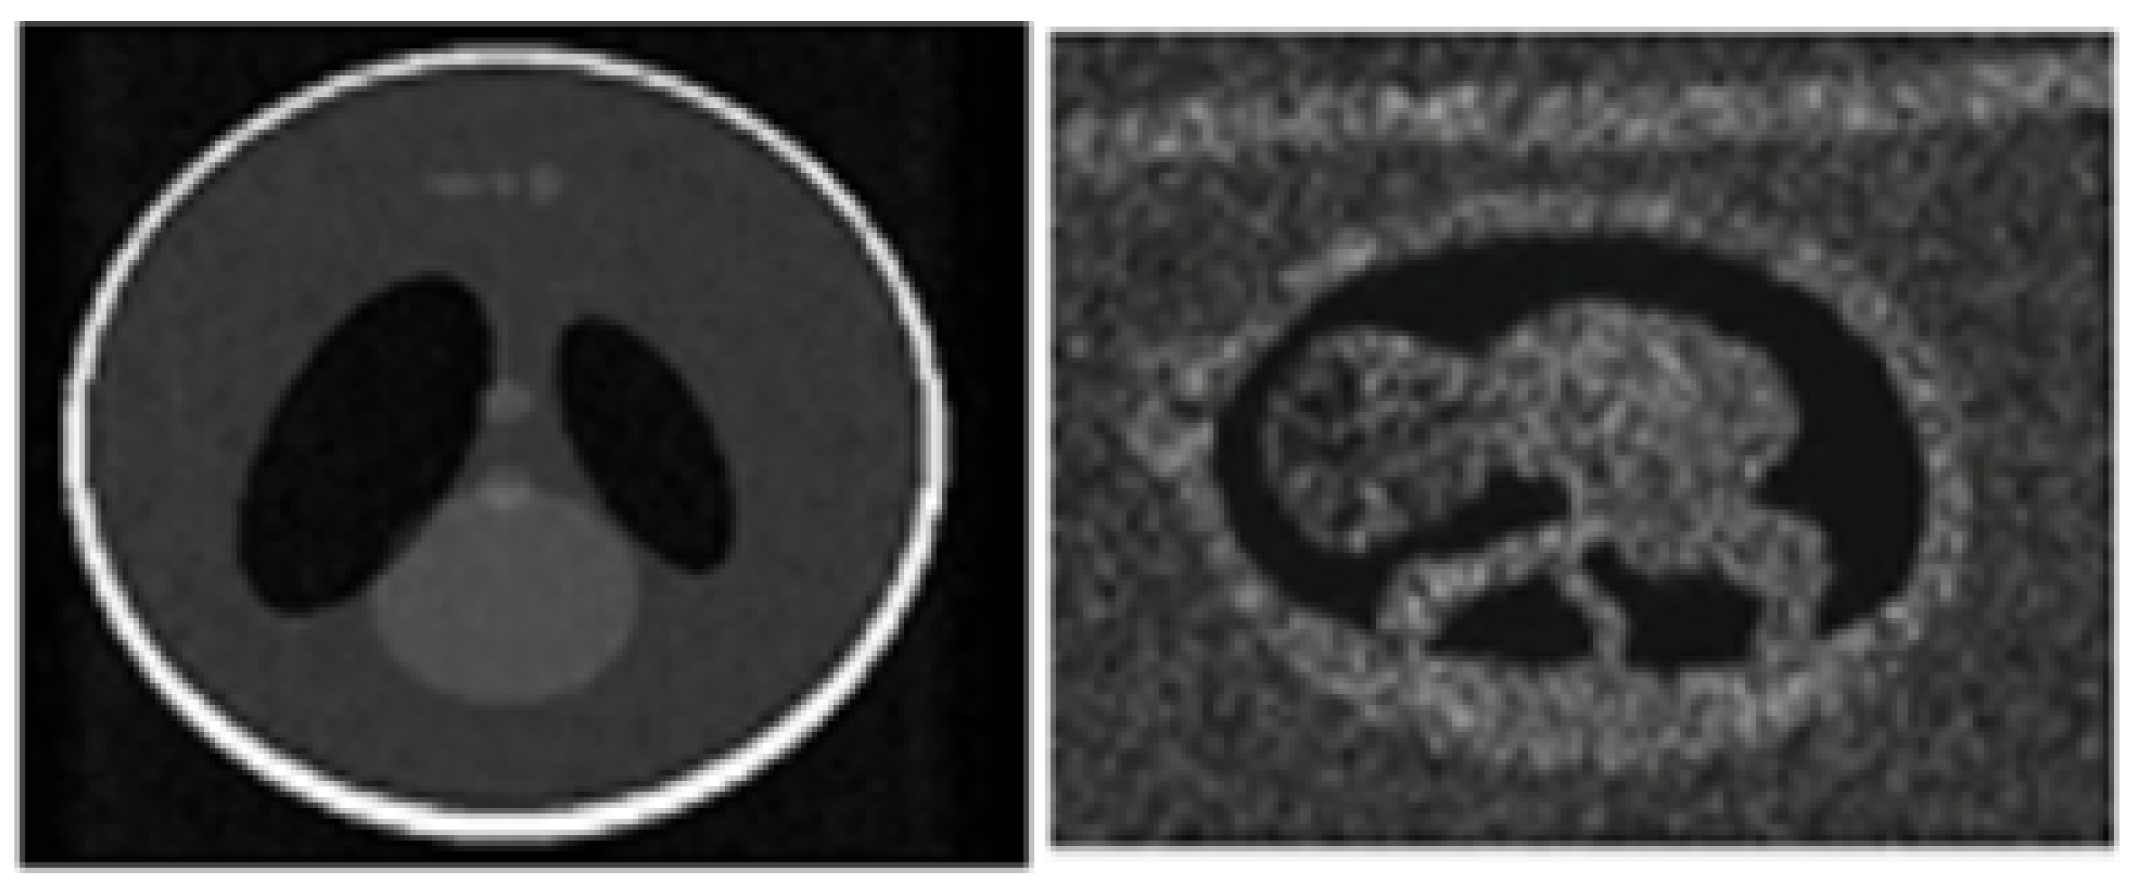

4.3. ISFWT-Based Pixel Coefficient Analysis

4.4. NIMWVSO-Based Noise Removal